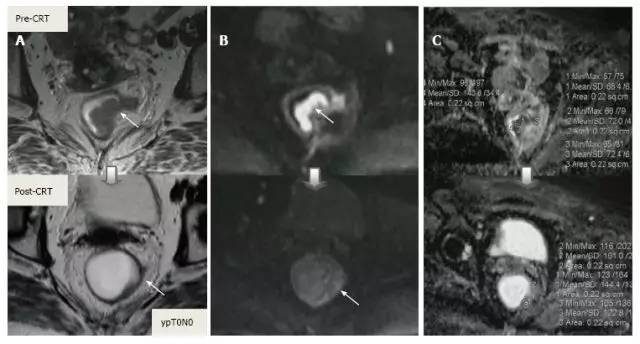

采用传统 MRI 序列对 CRT 后肿瘤重新分期的精确性差于初始分期,尤其在证实完全缓解(yT0),主要是很难将残留的肿瘤与纤维化、水肿和正常粘膜区分开,因此 CRT 后正常的 2 层直肠壁提示为完全缓解,而残留纤维化既可以是肿瘤残留也可以是完全缓解(图 17)。

实际上 CRT 后 T2 加权 MRI 后上纤维化的信号强度很低,而残留肿瘤区域则为中等强度,仔细评估高分辨图像和 DWI 是能区分小的残留病变和纤维化的(图 18)。

图片

图 17. 新辅助放化疗后肿瘤重新分期。在不同患者的 T2 加权 MR 图像上分别显示(上:治疗前,下:治疗后)。A. 在 ypT0 直肠肿瘤中,治疗后的轴位图像显示正常的两层直肠壁(箭头),对应完全缓解;B. 在 ypT3 直肠肿瘤中,治疗后的轴位图像显示正常的双层直肠壁(箭头)。这是 MR 评估完全缓解的假阴性例子;C. 在 ypT0 直肠肿瘤中,原有肿瘤区域治疗后呈现厚的、纤维化的低信号强度疤痕(箭头)。